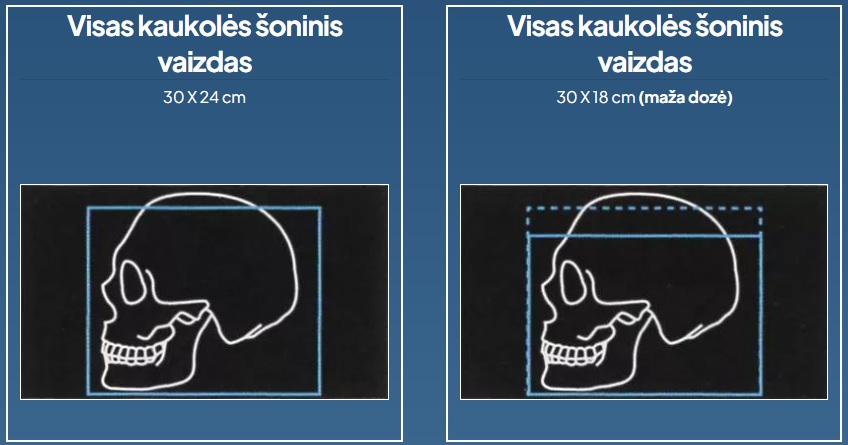

Intelektualūs cefalometriniai dantų panoraminiai vaizdai

Cefalometriniai rentgeno spinduliai, kurie prisitaiko prie jūsų poreikių ir siūlo žemos dozės programas.